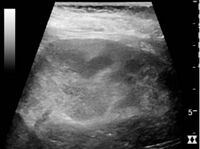

Cortical thickness should be estimated from the base of the pyramid and is generally 7–10 mm. If the pyramids are difficult to differentiate, the parenchymal thickness can be measured instead and should be 15–20 mm (Figure 3). The echogenicity of the cortex decreases with age and is less echogenic than or equal to the liver and spleen at the same depth in individuals older than six months. In neonates and children up to six months of age, the cortex is more echogenic than the liver and spleen when compared at the same depth.[1]

Figure 3. Measures of the kidney. L = length. P = parenchymal thickness. C = cortical thickness.[1]